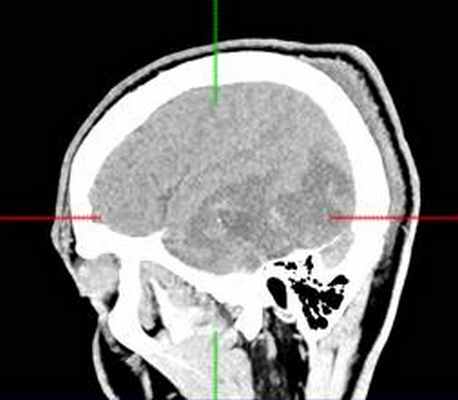

КТ головного мозга с контрастным усилением (24.03.2015): объемное кистозно-солидное образование правой теменно-височно-лобной области. Дислокационный синдром.